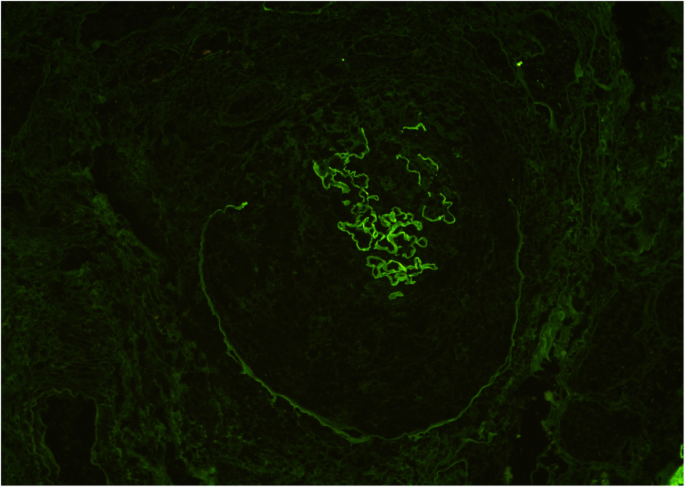

A 72-year-old Japanese man with hypertension and chronic kidney disease due to type 2 diabetes mellitus was referred to our medical center with worsening of the serum creatinine (sCr) level for 2 weeks. He had a baseline sCr of 1.1 mg/dL. The patient never smoked or had no family history of kidney or rheumatic disease. On examination, his respiratory rate was 24 breaths per minute, his heart rate was 73 bpm, his blood pressure was 125/64 mmHg, he had a saturation of 83% in room air, and his body temperature was 38.6 °C. Physical examination was remarkable for labored breathing using respiratory accessory muscles, bilateral coarse crackles, and pretibial pitting edema. There was no rash or purpuric skin lesion. Notable laboratory findings included severe anemia (hemoglobin level, 5.9 g/dL) and a markedly decreased kidney function (blood urea nitrogen (BUN), 182 mg/dL; sCr, 27.3 mg/dL; estimated glomerular filtration rate (eGFR) [6], 1 ml/min/1.73 m2). The immunoglobulin (Ig) levels were normal (IgM, 80 mg/dL; IgA, 196 mg/dL), except for elevation of IgG (1958 mg/dL). Urinalysis showed proteinuria (4.8 g/gCr) with microscopic hematuria (> 100 erythrocytes per high-power field) and a few red blood cell casts. Plain computed tomography showed bilateral pleural effusion and normal-sized kidneys. Antinuclear antibodies and proteinase 3 (PR3) and myeloperoxidase (MPO) antineutrophil cytoplasm antibodies (ANCA) were negative. Anti-GBM antibody was 476 units/mL. PR3-ANCA, MPO-ANCA, and anti-GBM antibody were measured using enzyme-linked immunosorbent assay method. Anti-GBM disease was confirmed by renal biopsy, which showed 10 glomeruli, seven of them had cellular crescent formation (Fig. 1) and three had global sclerosis. A moderate interstitial infiltration composed of monocytes and neutrophils was observed. Immunofluorescence microscopy showed linear staining for IgG along with the GBM (Fig. 2). Along with oral prednisolone (40 mg/day), double-filtration plasmapheresis (DFPP) using human albumin (5%) as the replacement material was initiated. The patient’s anti-GBM antibody decreased from 476 to 18 units/mL with twelve sessions of DFPP, but he underwent hemodialysis because his renal function did not recover. One month after completion of DFPP, however, the patient died from lung abscess (Fig. 3) caused by Pseudomonas aeruginosa.

A 32-year-old Japanese man, current smoker, presented with a 3-week history of fever with rigor and macroscopic hematuria. He denied hemoptysis, skin rash, or joint pain. Physical examination revealed his respiratory rate was 16 breaths per minute, his heart rate was 108 bpm, his blood pressure was 108/58 mmHg, and his body temperature was 39.0 °C. Other physical examinations were unremarkable. Laboratory tests showed mild anemia (hemoglobin level, 10.9 g/dL) and a moderately decreased kidney function (BUN, 35 mg/dL; sCr, 4.2 mg/dL; eGFR [6], 14 ml/min/1.73 m2). IgG was elevated (1110 mg/dL), but other immunoglobulin levels were normal (IgM, 68 mg/dL; IgA, 113 mg/dL). Antinuclear antibodies, PR3-ANCA and MPO-ANCA, using enzyme-linked immunosorbent assay method were negative. Urinalysis showed proteinuria (0.9 g/gCr) with microscopic hematuria (> 100 erythrocytes per high-power field). Plain computed tomography showed normal-sized kidneys and no alveolar hemorrhage. Anti-GBM antibody was 265 units/mL (enzyme-linked immunosorbent assay). Renal biopsy showed 12 glomeruli; all of them had cellular crescent formation (Fig. 4) and had no global sclerosis. Immunofluorescence microscopy showed linear staining for IgG along with the GBM (Fig. 5). Intravenous infusion of methyl prednisolone (500 mg/day for three consecutive days) followed by oral prednisolone (50 mg/day) was started. After completion of 20 sessions of DFPP using human albumin (5%), his anti-GBM antibody became undetectable. However, the patient’s kidney function did not recover, and he underwent hemodialysis. One year after the initial diagnosis, the patient’s anti-GBM antibody remained undetectable, and thus, he received living-donor kidney transplantation without recurrence of anti-GBM disease or other complications.